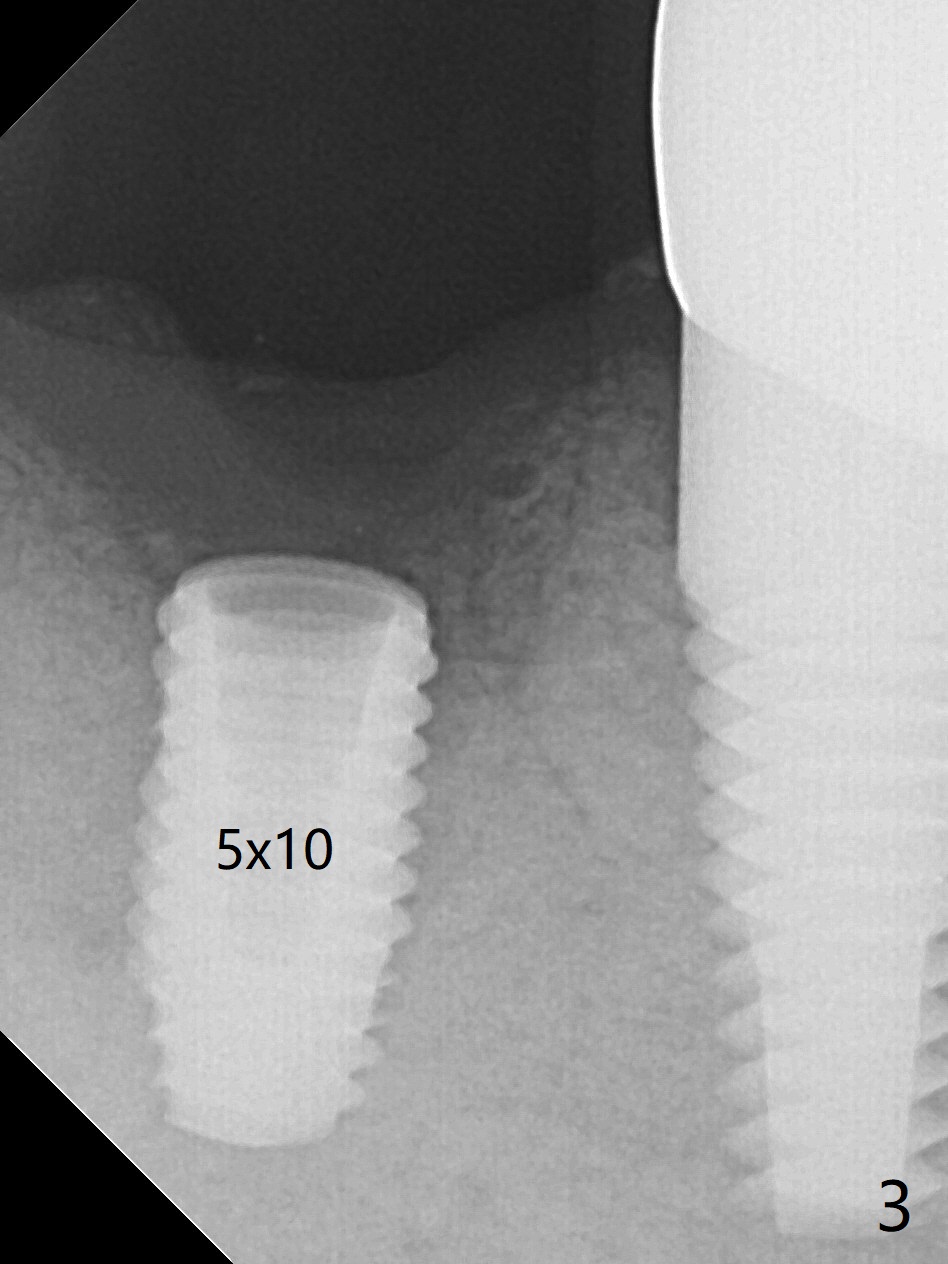

After 2.2x10 mm drill at #31 (Fig.1), bone expansion is conducted with 1.7/3.1 mm and 2.4/3.7 mm Expanders with guide (Fig.2) and 3.0/4.4 mm one without guide. Guided surgery resumes as planned to remove the lingual and apical bone. The buccal bone looks porous from the osteotomy opening. Mixture of autogenous and allograft is packed against the bone plate from the osteotomy before implant placement, but the 5x10 mm implant is unable to be seated completely. After removal of the bone graft from the osteotomy site and use of 4x11.5 mm drill for ~ 1 mm, the implant is seated with ~ 60 Ncm (Fig.3). With buccal incision, bone graft is placed over the distobuccal exposed implant thread (Fig.4 *) following placement of a 6x4 mm healing abutment. Oozing from the wound (thrombocytopenia) is controlled by Polysyn suture and perio glue (Fig.5). The mesial wound dehiscences 7 days postop when DO composite is placed at #28 (Fig.6). Two days later the patient returns because of hemorrhage in brushing. After placement of a taller healing abutment (6x7 mm) with triple antibiotic ointment (although the gingiva cuff is healthy), periodontal dressing is applied. Then the wound heals. The longer healing abutment remains seated (Fig.7 <) without interference from the crest (*) 4.5 months postop. A smaller cemented abutment (5.2x4(4) mm) is chosen with the same outcomes (well seated without gap (Fig.8 < between the implant and abutment), clearance from the crest (*)) 5 months postop. The final crown is cemented 6 months postop with distal access hole (Fig.9 black line), which may be related to design using normal 2nd molar tooth. In fact this patient has small teeth.